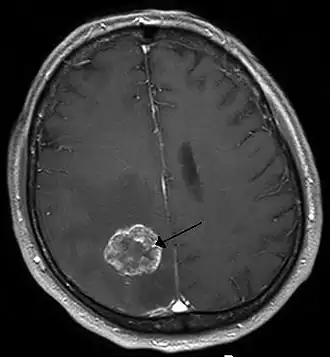

![]() Опухоль головного мозга. Визуализируется с помощью МРТ. | |